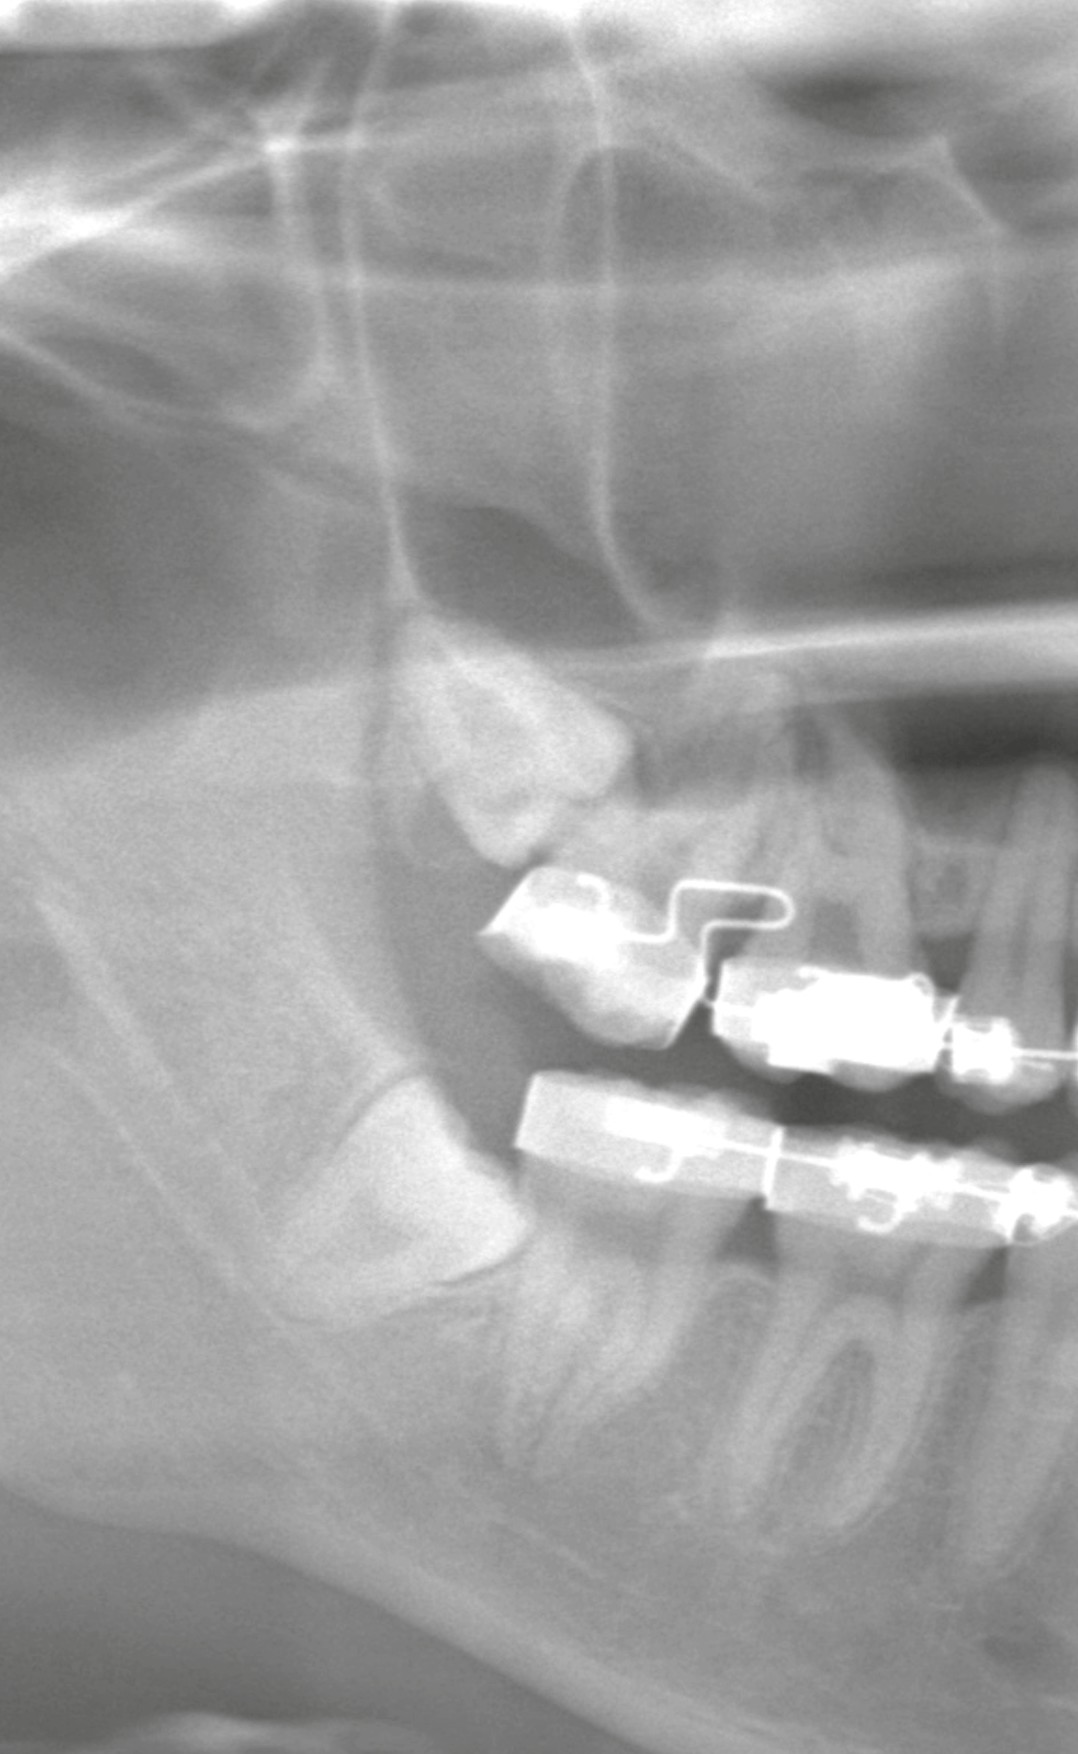

今回は、矯正治療中の患者さまが、矯正歯科からの紹介で親知らずを4本抜歯のケースとなります。

CTで見ると、親知らずの根の先が上顎洞にかなり近接していました。

矯正治療中のため、大きく歯肉を切開し視野を確保することが難しい。

上顎の抜歯は割とすぐ終わるのですが、今回のケースは完全埋伏しているケースであり、上顎洞に近接+矯正器具により視野確保困難などの要素が加わり、慎重に時間をかけながら実施しました。